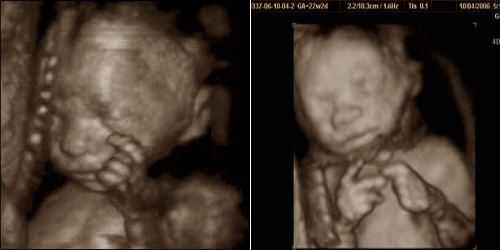

Это результат размягчения связок и суставов в сочетании с повышенной нагрузкой на ноги изза увеличения веса. Вносят свою лепту и отеки. Стопа может прибавить размера, но не стоит переживать после родов она вернется в норму. Если вы еще не прошли второе плановое. УЗИ, на неделе беременности самое время это сделать. Ребенок уже сформирован, похож на полноценного человека, можно разглядеть его лицо, определить пол. На неделе врач назначит вам очередной визит, во время которого оценит ваше самочувствие, течение беременности, при необходимости назначит дополнительные исследования и анализы. Выделите ее и нажмите.

Ольга. Была на втором узи, неделя беременности, вес гр, будет мальчик уже второй, первого в родила. УЗИ написали гиперэхогенн ость кишечника плода. У когонибудь было такое. Читала много про это, не знаю что и думать. Завтра на явку иду, буду со своим гинекологом беседовать об этом. В ответ на комментарий от декабря. УЗИ показало осадок околоплодных вод. Пожаловатьсяа что вам врач сказала у меня по. УЗИ неделитоже показало мелкодисперсную взвесь в водах.